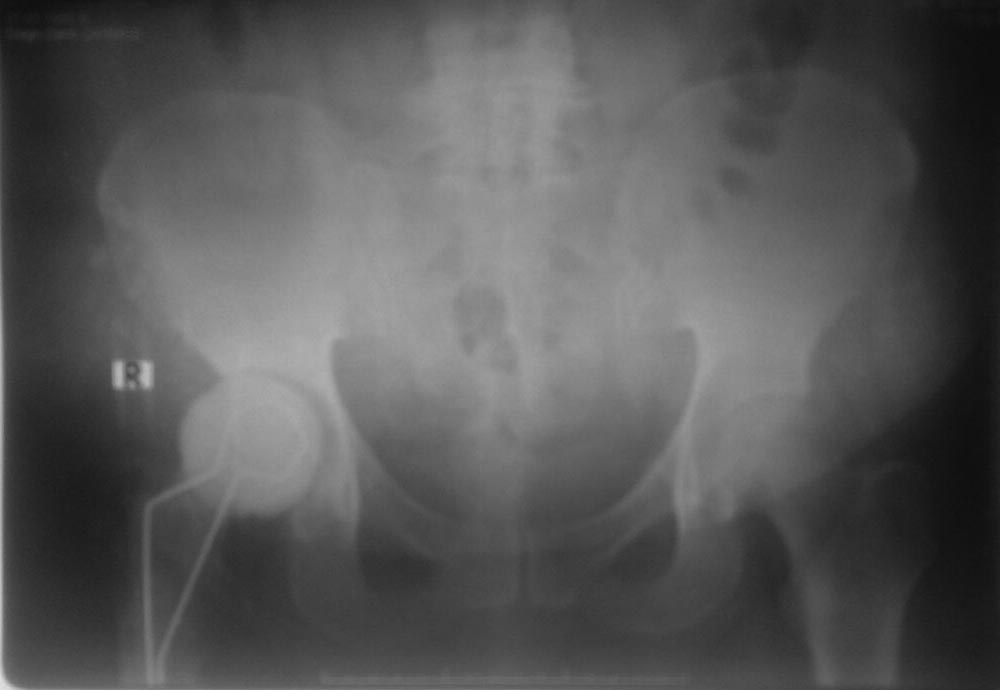

Добрый день, Сергей. В данном случае однозначно надо ревизовать, удалить останки цемента. У нас такие случаи были и были времена, что инструменты тоже не были. Цемент можно удалить с помощью развертки для канала (сверлом). Затем цементный спейсер с гентамицином на 2-3 месяца (может быть, неоднократно). После контроль анализов, пункция сустава на чувствительность. Если все нормально -реэндопротезирование сустава. Удачи!